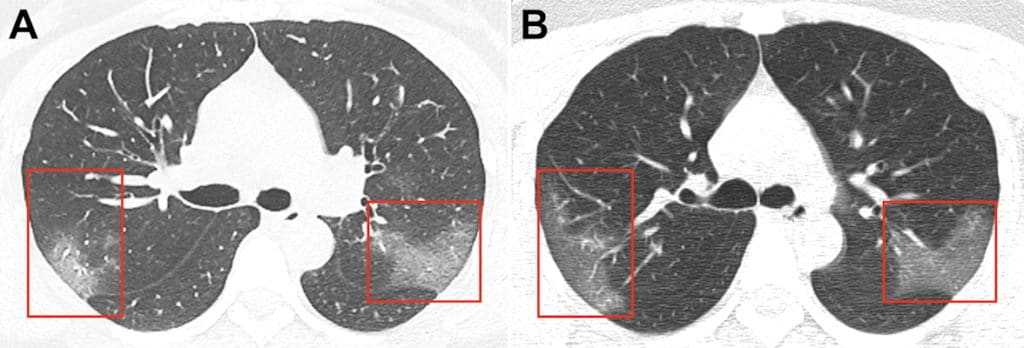

Симптом «матового стекла» (инфильтраты) при вирусной пневмонии на посрезовых КТ-сканах

Многочисленные уплотнения легочной ткани по типу «матового стекла» преимущественно округлой формы, различной протяженности с/без консолидации, локализуются, большей частью, в периферических, кортикальных отделах, мультилобарные. Поражение чаще носит двусторонний характер (в настоящее время описаны только единичные случаи одностороннего поражения).

Очаги поражения легких при COVID-19

К дополнительным признакам относятся:

- утолщение междолькового интерстиция по типу «булыжной мостовой» (англ. «crazy-paving» sign)

- участки консолидации

- перилобулярные уплотнения

- симптом воздушной бронхограммы

Указанные признаки преимущественно определяются на 5–12 сутки заболевания.